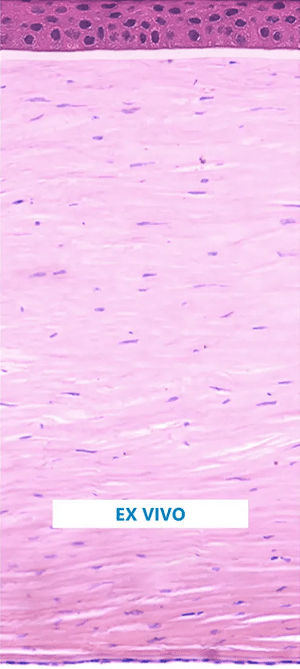

Pentacam® Cornea OCT TC